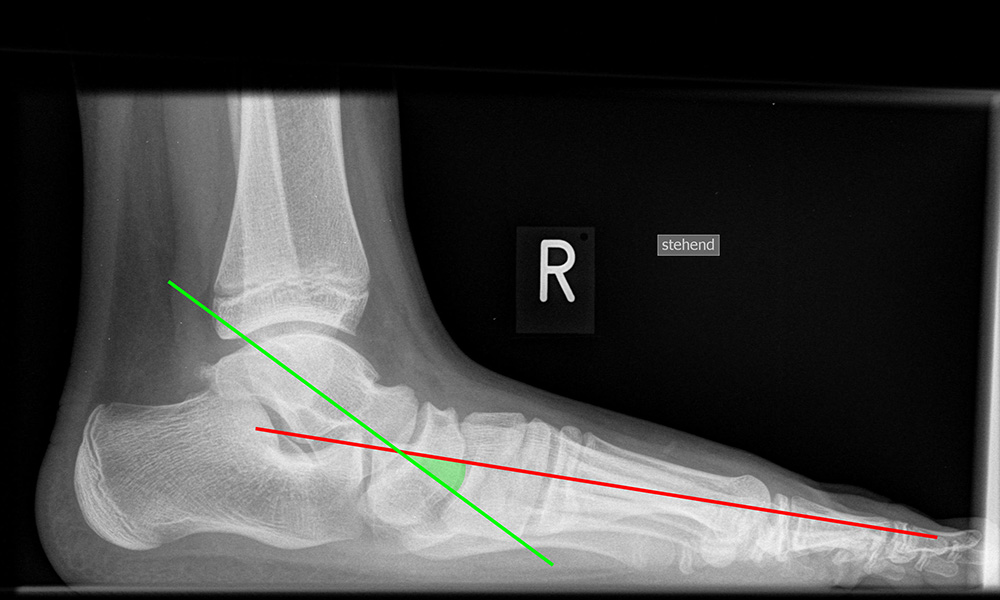

Fuß seitlich mit Belastung

Kennzeichen des Röntgenbildes:

• Standardabbildung des Fußes zusammen mit der belasteten d.-p. Aufnahme und der unbelasteten 45° Pronationsaufnahme.

• Überblick über die Fußanatomie und Fußstatik.

• Die seitliche Aufnahme liefert Informationen zur Stabilität des Längsgewölbe und zu den Achsen von Talus, Kalkaneus und Metatarsale I.

• Die Aufnahme wird eingesetzt zur Darstellung von freien Gelenkkörpern sowie knöchernen Veränderungen am Achillessehnenansatz oder der Plantarfaszie.

Besondere Bemerkungen zum Beispielbild:

• Schwere Hallux valgus Deformität.

• Die Sesambeine sind luxiert, ebenso das Großzehengrundgelenk. Luxation des Metatarsophalangealgelenks II.

• Degenerative Veränderungen der tarsometatarsalen (TMT) Gelenkreihe, betont TMT II und III.

Beurteilung von Fehlstellungen des Mittel- und Rückfußes

Zur Vollansicht und zum Lesen der Bildbeschreibung bitte die Bilder anklicken.

Achsen auf der lateralen Aufnahme

Die Grundlinie (blau) ist definiert durch den tiefsten Punkt der Sesambeine und den tiefsten Punkt des Kalkaneus.

CPA (Calcaneal pitch angle): Der Kalkaneus Inklinationswinkel liegt zwischen der Grundlinie (blau) und der plantaren Begrenzung des Kalkaneus (grün) (Norm 20,8 ± 4,1° 11, 15-39° (Zwipp 2014)).

LTCA (Lateral talocalcaneal angle): Der laterale talokalkaneare Winkel liegt wird gebildet aus der Talusachse (türkis) und einer Verbindungslinie zwischen dem Oberrand des Proc. ant. Calcanei und der dorsalen Begrenzung des Kalkaneus (gelb). (Norm: 33° Range 25-45°) 1213).

LTMA (Lateral talometatarsal angle, Syn. Meary’s angle): Der laterale talometatarsale Winkel wird gebildet aus der Achse des Os metatarsale I (rot) und der Achse des Talus (türkis). (Norm: 7,1 ± 10,8 11).

Böhler-Winkel (Syn. Tubergelenkwinkel)

Es wird eine Linie vom Proc. ant. calcanei zur dorsalen Facette des Subtalargelenks gezogen (rot). Die zweite Linie verläuft von der kranialen Begrenzung des Tuber calcanei zum Subtalargelenk (gelb). Gemessen wird der nach dorsal offene Winkel zwischen den beiden Linien (Norm: 22-48° 9).